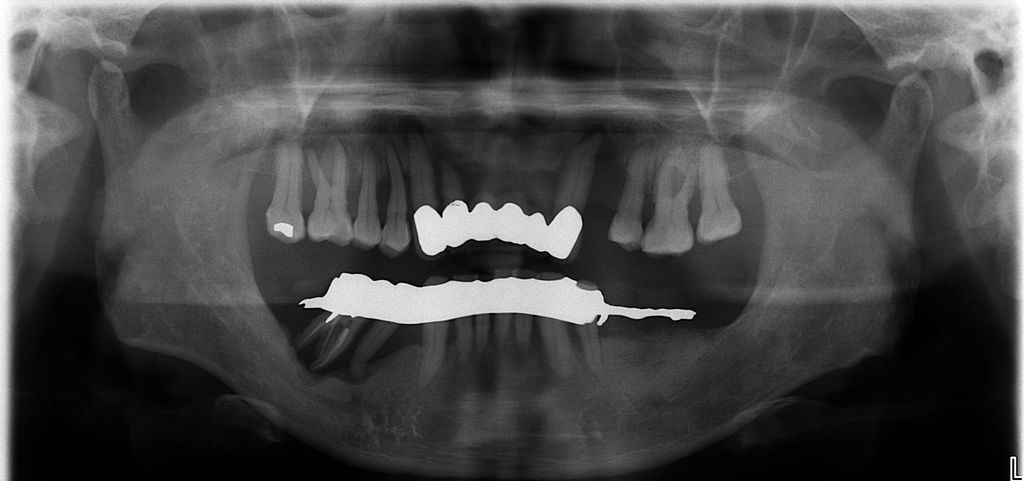

既然之前看了那麼多活動假牙的文章,今天趁著颱風假的空檔跟大家聊聊植牙,偶爾換換口味才不會那麼膩。植牙很多部份大家都提過了,沒什麼新鮮的,不外乎補骨、補肉、做假牙。那我只能談談病人的抱怨:「沈醫師,為什麼我做假牙要來那麼多次」。很多人都有在牙科做過假牙的經驗,一般不外乎是印模、裝假牙,兩次就好。也沒錯啦!一般比較簡單的case或是一兩顆的植牙簡單處理一下是可以,所以病人一開始來的時候都會問,「我們什麼時候要印模」以為印了模之後故事就要結束了,沒想到遇到我,印了模之後故事才要開始…